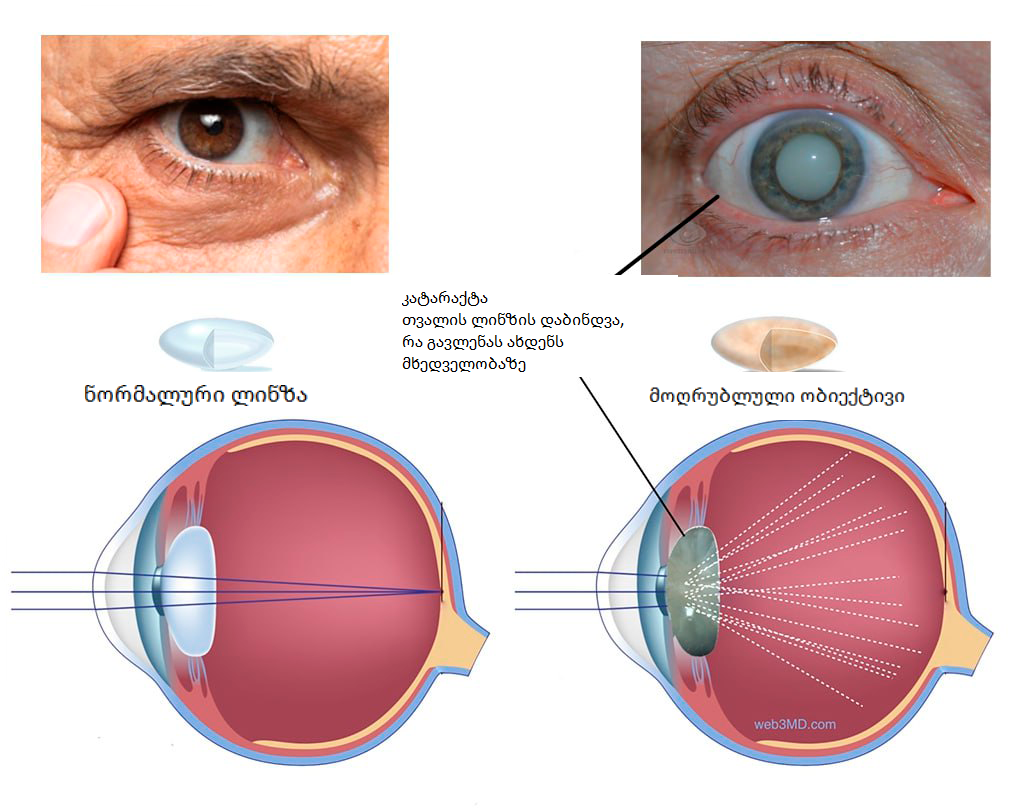

ინტერნეტიდან: ბადურის დისტროფია, არსებითად, არ არის ცალკეული დაავადება, არამედ დაავადებათა მთელი კომპლექსი, რომელიც ასე თუ ისე წარმოდგენილია ბადურის დეგენერაციული დაზიანებით ან მისი განუვითარებლობით. ჩვეულებრივ ვითარდება ასაკთან ერთად, რაც იწვევს თვალის ლინზის კატარაქტს და სრულ სიბრმავეს.

რეგისტრირებული სხვა ექიმთან. მან ასევე გააკეთა კატარაქტის ჩემს დიაგნოზთან. და ეს არის სერიოზული რამ-კატარაქტა ხშირად ადასტურებს სრულ სიბრმავეს. და ეს სულაც არ არის ხუმრობა. მარტო ვცხოვრობ კაცის გარეშე, თითქოს 23 წელია განქორწინებული ვარ. ბავშვები გაიზარდნენ, რომლებიც სად წავიდნენ. ვის ვჭირდები უსინათლო ინვალიდი?